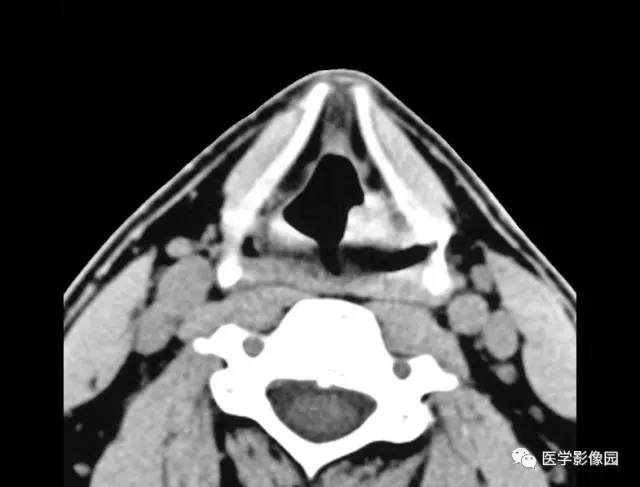

3.声带和室带可不规则增厚或形成软组织肿块(图3-5-10)。

4.病灶周围喉旁间隙多正常,常不向深部浸润,成人如有深部浸润应提示有恶变可能。

图3-5-10 喉乳头状瘤A.B.

CT平扫见左侧室带后部局限性软组织肿块,

并向喉腔突入(↑),喉旁间隙显示清晰